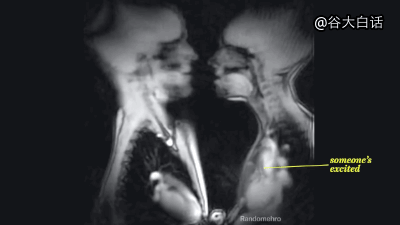

#爱你爱到骨头里#【MRI下诡异而奇妙的人体】这是一段用核磁共振成像技术制作的动态短片,将人类喝水、亲嘴、嘿咻、拉翔、生娃、说中文、说德文等日常活动展现得毫纤毕现、一览无遗。doge微猎奇,微暴,慎点。